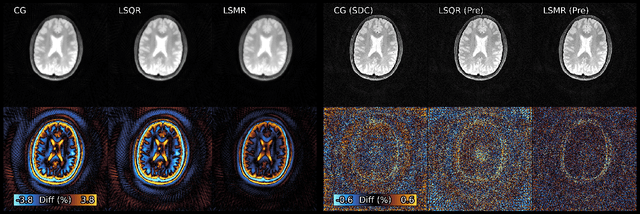

Figure 3 for Algorithms for Least-Squares Noncartesian MR Image Reconstruction